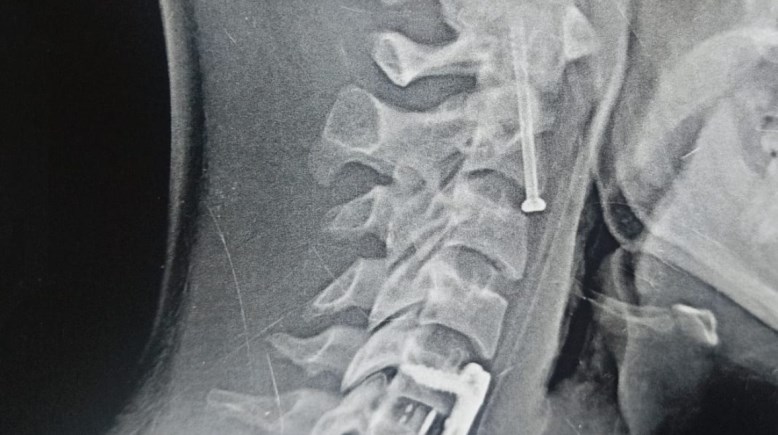

سقط على رقبته، جراحة دقيقة بمستشفيات جامعة بنها تنقذ مريضًا من الشلل